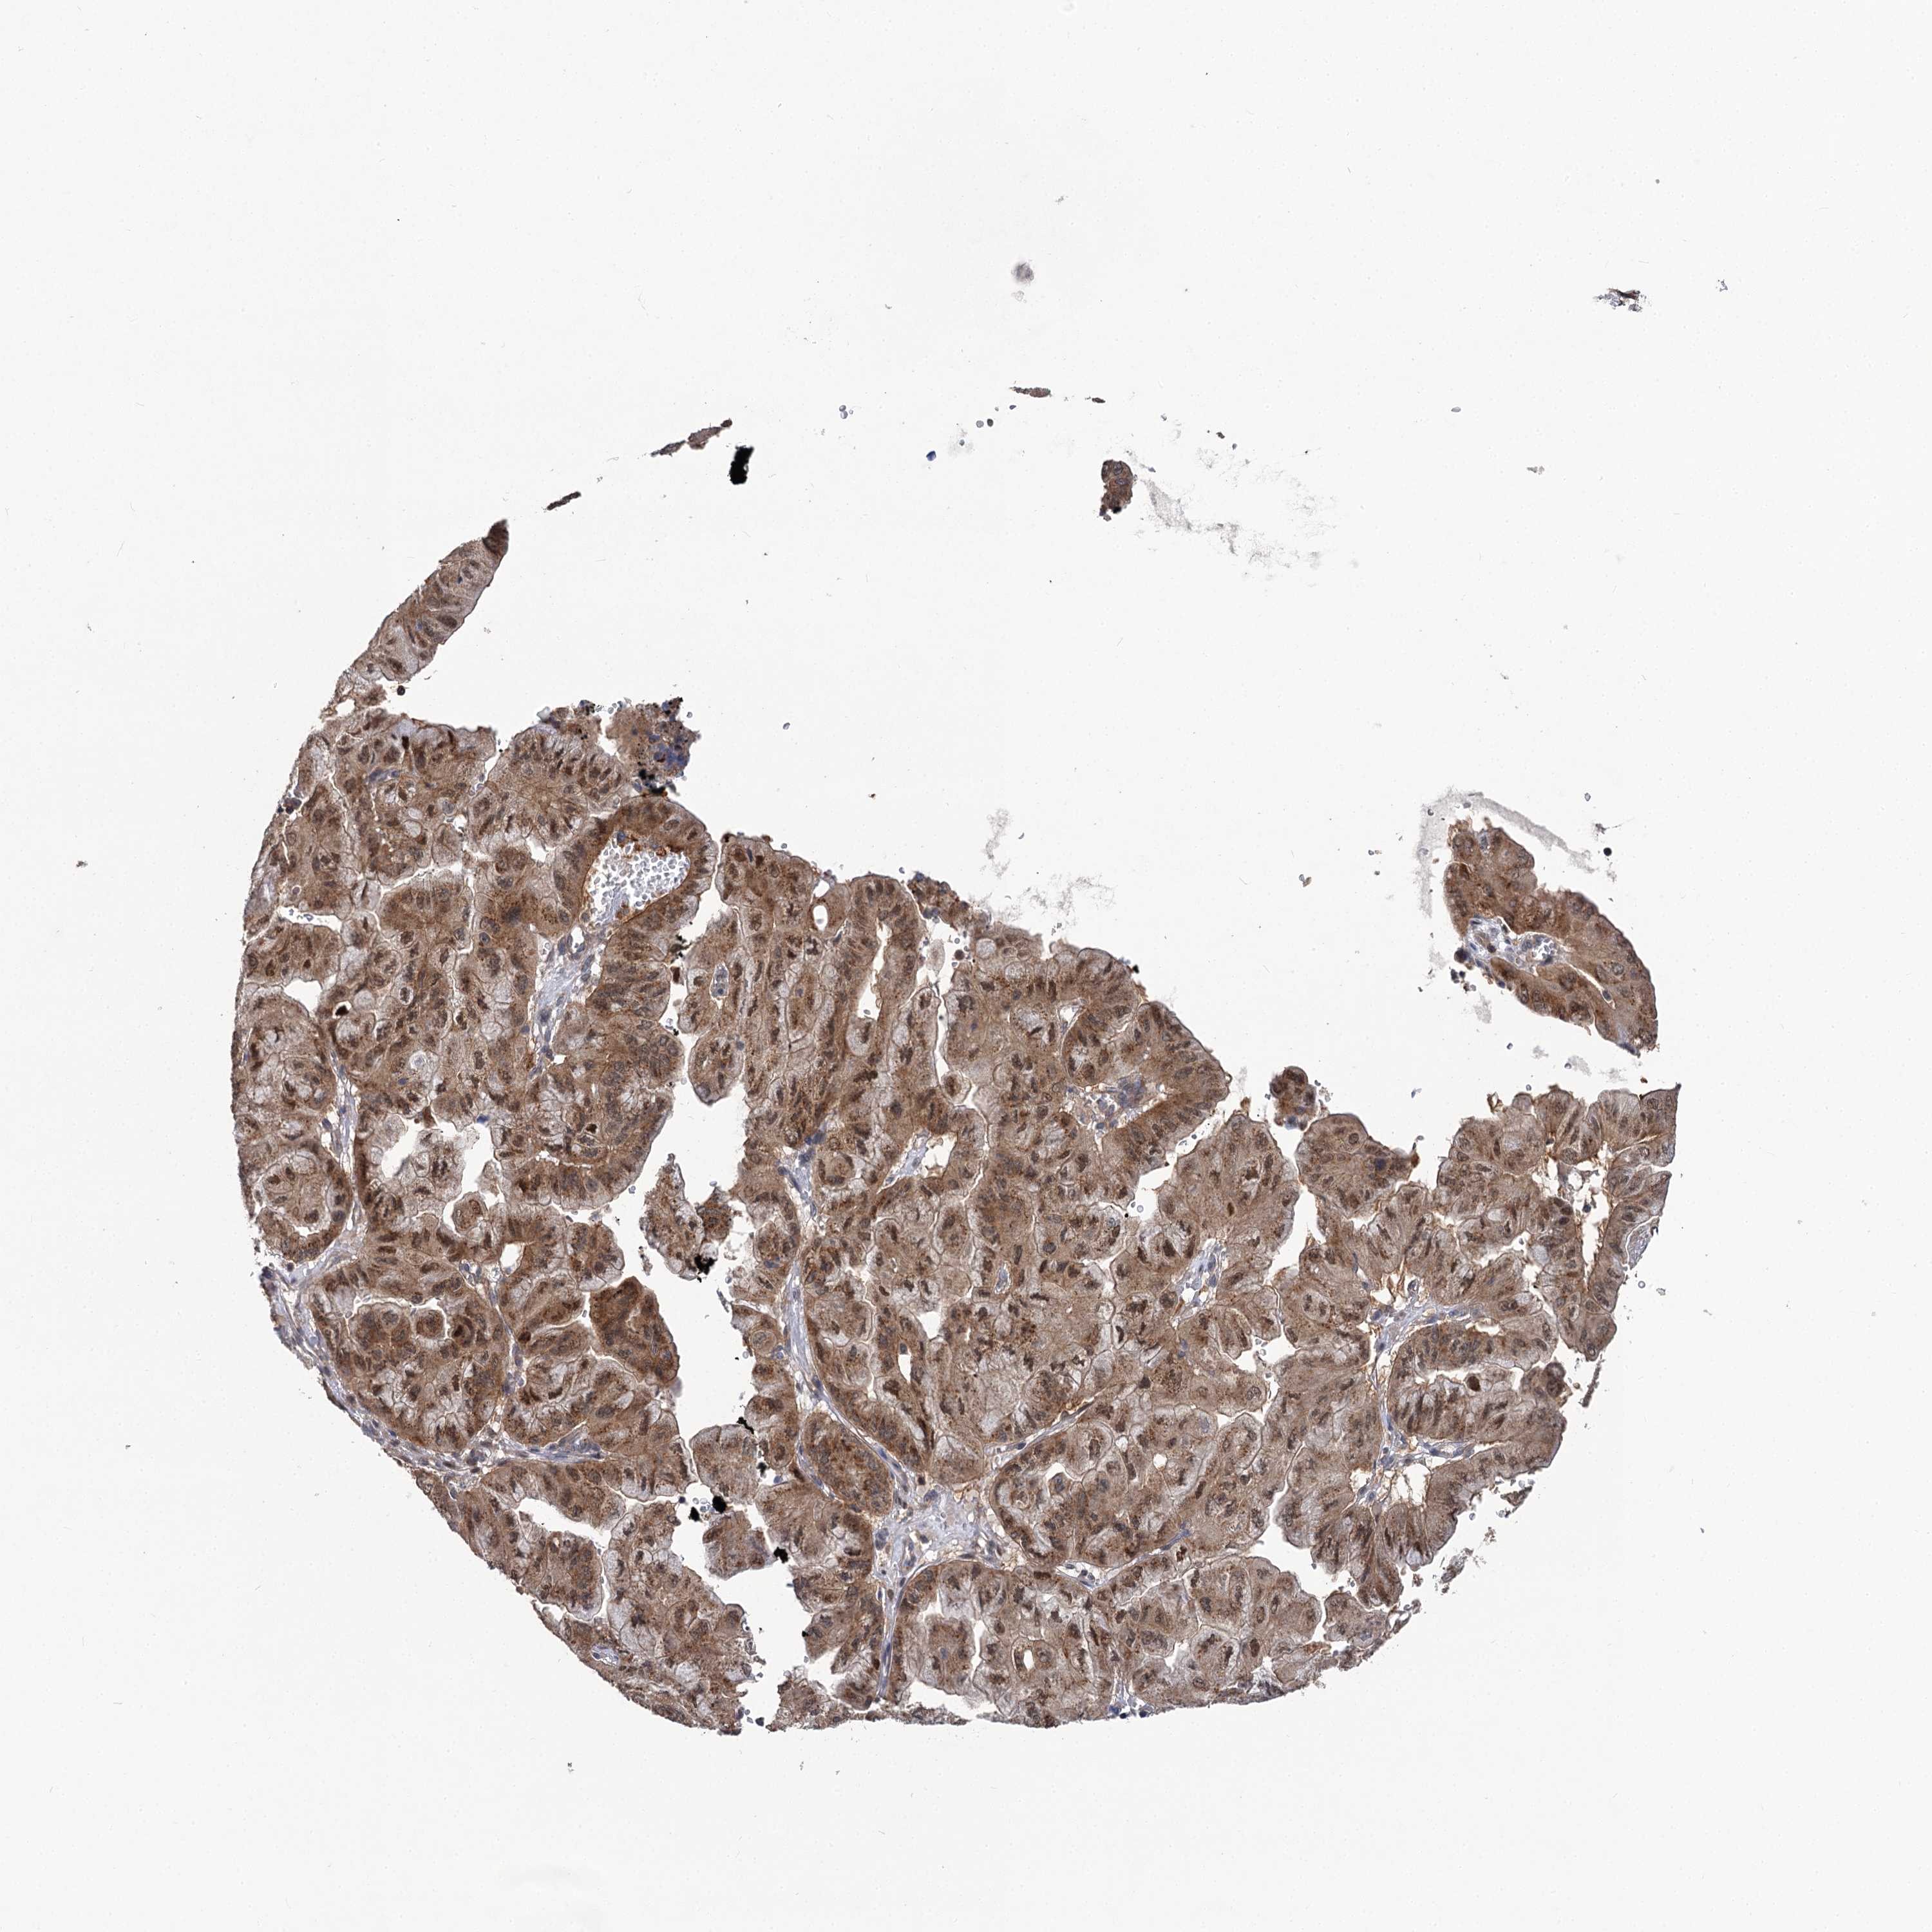

PANCREATIC CANCER - Protein expressioni

A mouse-over function shows sample information and annotation data. Click on an image to view it in a full screen mode. Samples can be filtered based on level of antibody staining by selecting one or several of the following categories: high, medium, low and not detected. The assay and annotation is described here.

Note that samples used for immunohistochemistry by the Human Protein Atlas do not correspond to samples in the TCGA dataset.

Antibody stainingi

Antibody staining in the annotated cell types in the current human tissue is reported as not detected, low, medium, or high, based on conventional immunohistochemistry profiling in selected tissues. This score is based on the combination of the staining intensity and fraction of stained cells.

Each image is clickable and will lead to virtual microscopy that enables deeper exploration of all samples and also displays staining intensity scores, fraction scores and subcellular localization as well as patient and tissue information for each sample.

Antibody HPA038557

Antibody HPA038558

Staining

High

Medium

Low

Not detected

Intensity

Strong

Moderate

Weak

Negative

Quantity

>75%

75%-25%

<25%

None

Location

Nuclear

Cytoplasmic/membranous

Cytoplasmic/membranous,nuclear

Adenocarcinoma, NOS